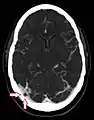

Angiografía por TC que muestra una granulación aracnoidea en el seno transverso derecho